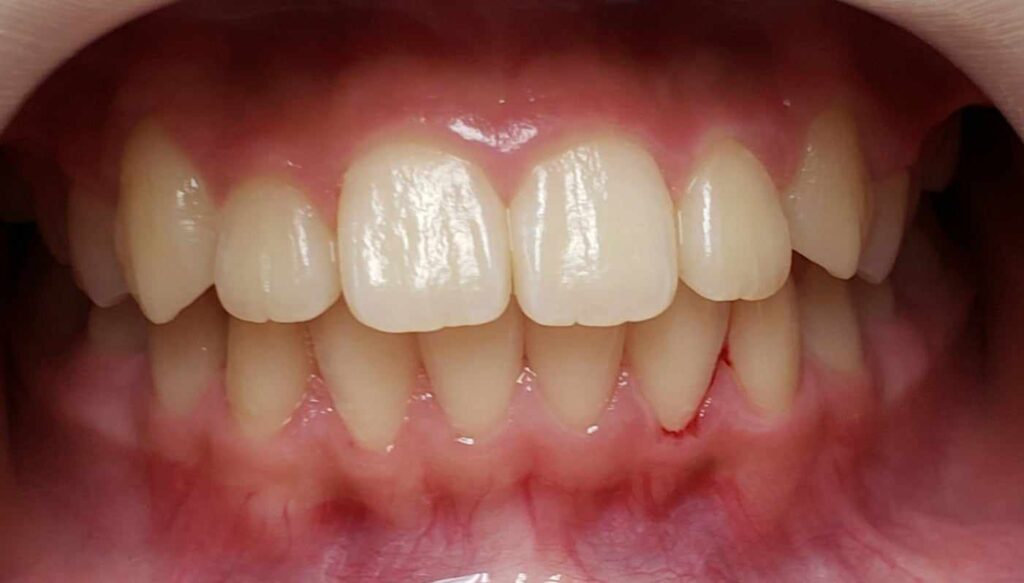

治療前

- 初診:2016年、9歳女児

- 主訴:出っ歯と歯の隙間がきになる。

- 診断:2級過蓋咬合、上下永久歯(犬歯)萌出スペース不足

- 治療方針:非抜歯で行う。虫歯予防(フッ素)、歯磨き指導、上下拡大床→咬合関係改善のツインブロック(2級→1級関係へ)→マウスピース矯正→下親知らずの抜歯、保定→メンテナンス